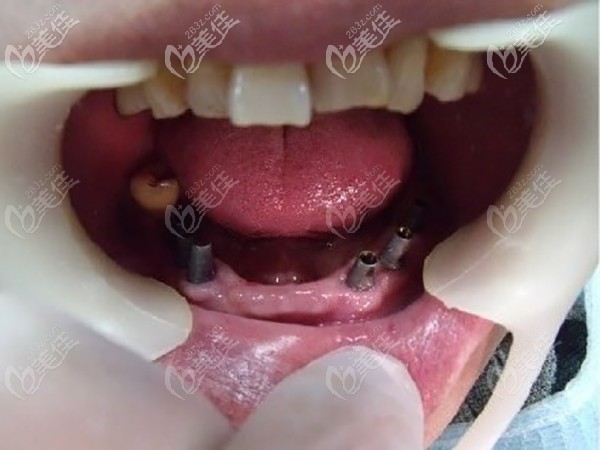

种植体:德国icx ALL-ON-6种植修复。

在麻药的作用下,很快就种好牙齿,医生说术后根据个人体质不同,有的人没感觉,有的人只会有轻微肿胀不适,不会有很大的疼痛,老人说他自己没啥感觉。

老人戴完牙冠后,自己还是比较满意的,昆明柏德口腔种植牙价格在当地收费还是比较合理的,重要的是老人能有一口吃啥都香的牙齿,儿子没有花多少钱就体现了孝心,还有比这更好地事情么?